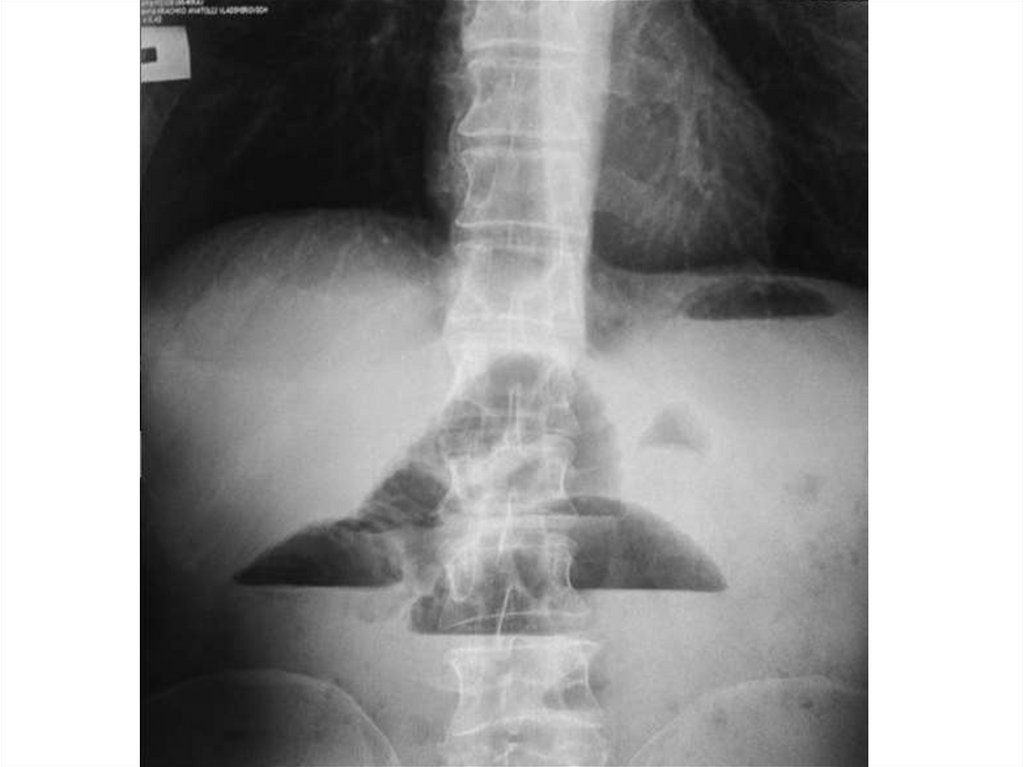

На рентгенограмме грудного отдела

позвоночника в прямой проекции стоя

определяется отклонение оси

позвоночника вправо с

формированием сколиотической дуги

на уровне Th6-Th11, угол сколиоза 1100

(4 степень сколиоза)

На рентгенограммах грудного и поясничного отделов позвоночника в

двух проекциях лёжа отклонение оси позвоночника влево на уровне Th4Th12, угол сколиоза 650 (4 степень сколиоза) с правосторонней

противодугой на уровне Th12-L4, угол сколиоза 450. Признаки

патологической ротации тел позвонков 4 степени. Грудной кифоз усилен

(угол кифоза 720). Вентральная клиновидность тел грудных позвонков на

высоте кифоза. Снижение высоты межпозвонковых дисков.